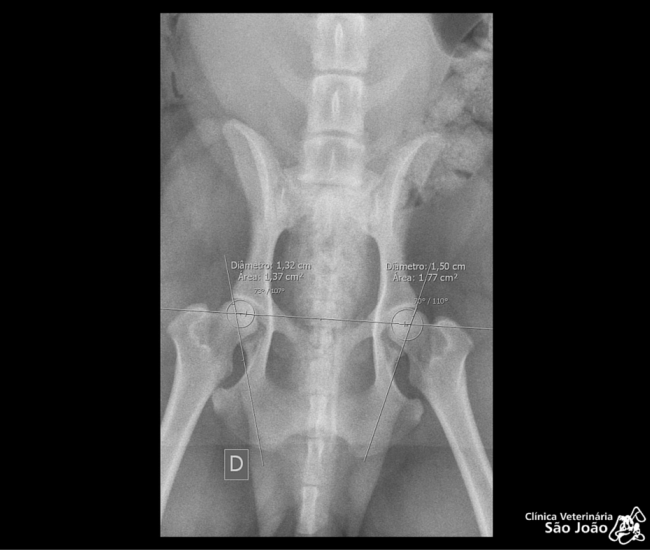

- Diferentemente do raio-x analógico, este raio-x oferece altíssima definição e todas as vantagens da tecnologia digital. É possível aproximar a imagem, trabalhar o contraste, exposição.O software permite ainda avaliações da medida cardíaca do animal e graus de displasia coxofemoral, por exemplo – explica o Dr. Nardeli Lucena.

- sofware com medidas para avaliações do tamanho cardíaco e medições dos ângulos de Norberg para diagnóstico e classificação de displasias coxofemorais;